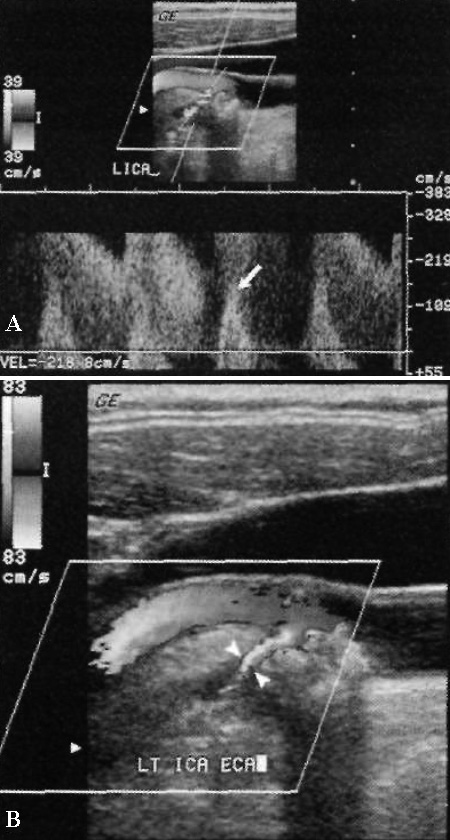

Эффект смешивания при исследовании сонных артерий определяется как с помощью цветовой, так и с помощью спектральной допплерографии в момент визуализации максимальной скорости кровотока. Так, на спектральной допплерографии максимальные скорости «обрубаются» и смещаются вниз от изолинии, а на цветовой допплерографии наблюдается искажение изображения вокруг четырехцветного контура, включая красный, желтый, зеленый и синий цвета (фото 5).

УЗИ: Тяжелый стеноз внутренней сонной артерии на уровне бифуркации

Фото 5. Тяжелый стеноз внутренней сонной артерии на уровне бифуркации. А – значительное увеличение максимальной скорости кровотока > 380 м/с. Наблюдается эффект смешивания: стрелкой обозначен систолический пик, который закручивается и смещается ниже изолинии. Курсором отмечен показатель увеличенной конечно-диастолической скорости до 218 см/с. Скорость потока в общей сонной артерии составляет 50 см/см, соответственно, значение отношения скоростей внутренней и общей сонных артерий составляет 7,6, что свидетельствует о стенозе очень высокой степени (80-99%). В – цветовая допплерограмма того же больного: указателями отмечено выраженное сужение внутренней сонной артерии атеросклеротической бляшкой

Также нужно обратить внимание на отличие обратного тока крови от смешивания. Обратный ток крови – это двунаправленное движение крови в плоскости изображения. В норме он определяется на уровне луковицы сонной артерии (в месте расширения сосудов), вызывая нарушение ламинарного потока крови. Цветовая допплерография демонстрирует только два цвета, которые разделены черным цветом, – красный и синий, обозначающие поток крови по направлению к датчику и от него. В области обратного кровотока показатель скорости остается в норме. Эффект смешивания обусловлен скоростями потоков, которые превосходят частоту смены кадров. При условии правильной настройки оборудования область смешивания визуализируется как зона очень высокой скорости кровотока. Таким образом, этот прием используют с целью выявления наиболее стенозированного участка сосуда (фото 6).

Фото 6. Обратный поток крови и эффект смешивания. Исследование внутренней сонной артерии: стрелками обозначен внутренний поток крови (красный и синие цвета с черной линией, которая их разделяет); указателями отмечен эффект смешивания в центре просвета луковицы сонной артерии (переход от красного к желтому и от голубого к синему)